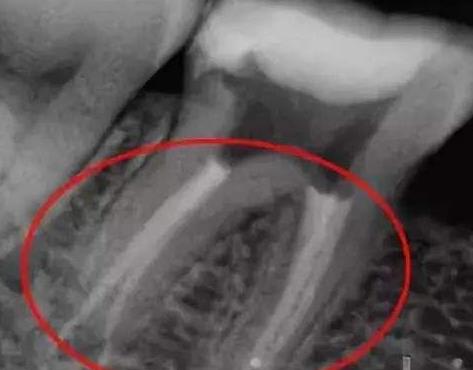

根管治療後複發通常會(hui) 在治療結束後近期或者遠期出現叩痛、咀嚼痛,持續性陣痛(有的人受不了)以及牙齒鬆動等症狀。出現這些情況後建議大家一定要及時到醫院拍個(ge) 牙片,看看牙齒根管充填的情況,根尖有無陰影,是否發展為(wei) 根尖等。

根管治療後拍片

根管治療超充、欠充在牙片上的顯示